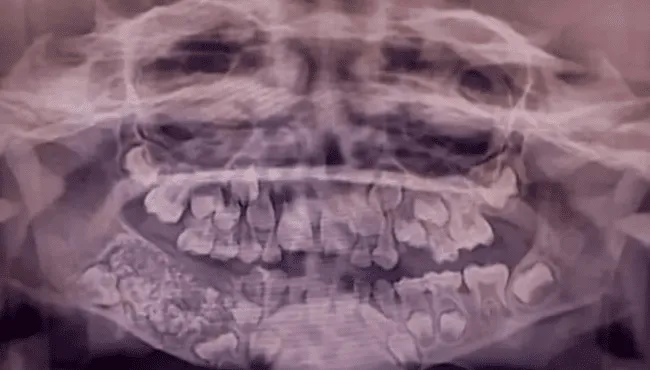

Los estudios radiográficos y las tomografías mostraron una masa de cerca de 200 gramos en el interior de la mandíbula. El Dr. Senthilnathan, jefe del Departamento de Cirugía Oral y Maxilofacial, determinó que se trataba de un “odontoma compuesto”, un tipo de tumor benigno relacionado directamente con la formación dental.

El resultado sorprendió incluso a los profesionales con mayor experiencia. De acuerdo con Science Alert, el saco contenía 526 piezas dentales en miniatura que variaban entre 0,1 milímetros y 15 milímetros de longitud. El proceso de clasificación y conteo de cada diente tomó cinco horas adicionales de trabajo de laboratorio.

La Dra. Pratibha Ramani, directora del área de Patología Oral y Maxilofacial, resaltó que todas las piezas extraídas poseían las características propias de un diente normal: corona, raíz y esmalte. “Incluso la pieza más pequeña tenía las características de un diente tradicional”, precisó la especialista, remarcando que no existen antecedentes con tal cantidad de dientes en registros médicos internacionales.